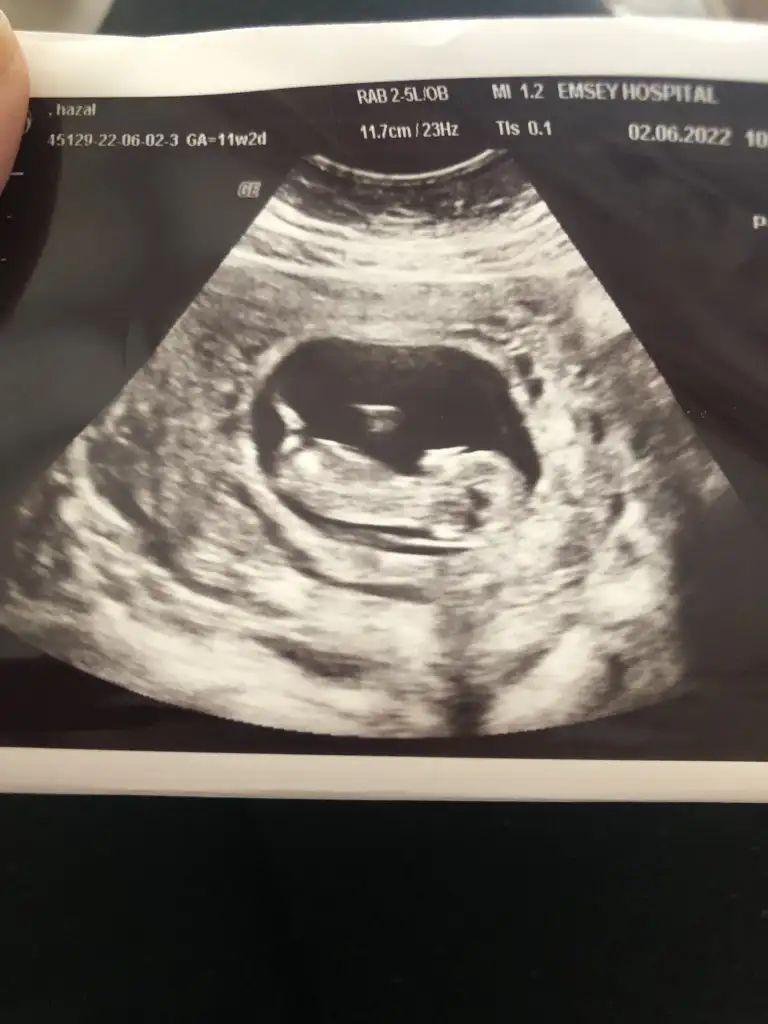

Merhaba nursu 11 haftalik atmistim prenses gibi demistin bugün 13 +2 hafta olduk özel hastanede doktor %90 erkek dedi son foto attım yeniden baksana

8+4 günlük karından ultrason tahmininizi soylermisnz